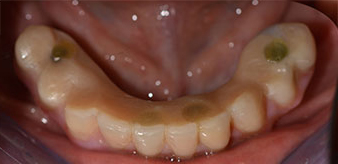

The impression and bite registration were then performed so that the dental technician could begin producing the provisional restoration immediately. This was then screwed in on the same day (Fig. 17 and 18).

Following the time required for the osseointegration, the final impression of the implants could be performed and the final denture produced accordingly (Fig. 19 and 20). At this point, the dentist and patient were able to decide together whether to use a ceramic or acrylic veneer and a zirconium or metal framework. In this case, Dr. Pascu’s team decided on an acrylic veneer based on the unclear prognosis for the maxillary dentition and the fact that tooth 24 is elongated. This type of veneer is generally considerably easier to adapt and can thus be subsequently altered to reflect the new situation in the maxilla.